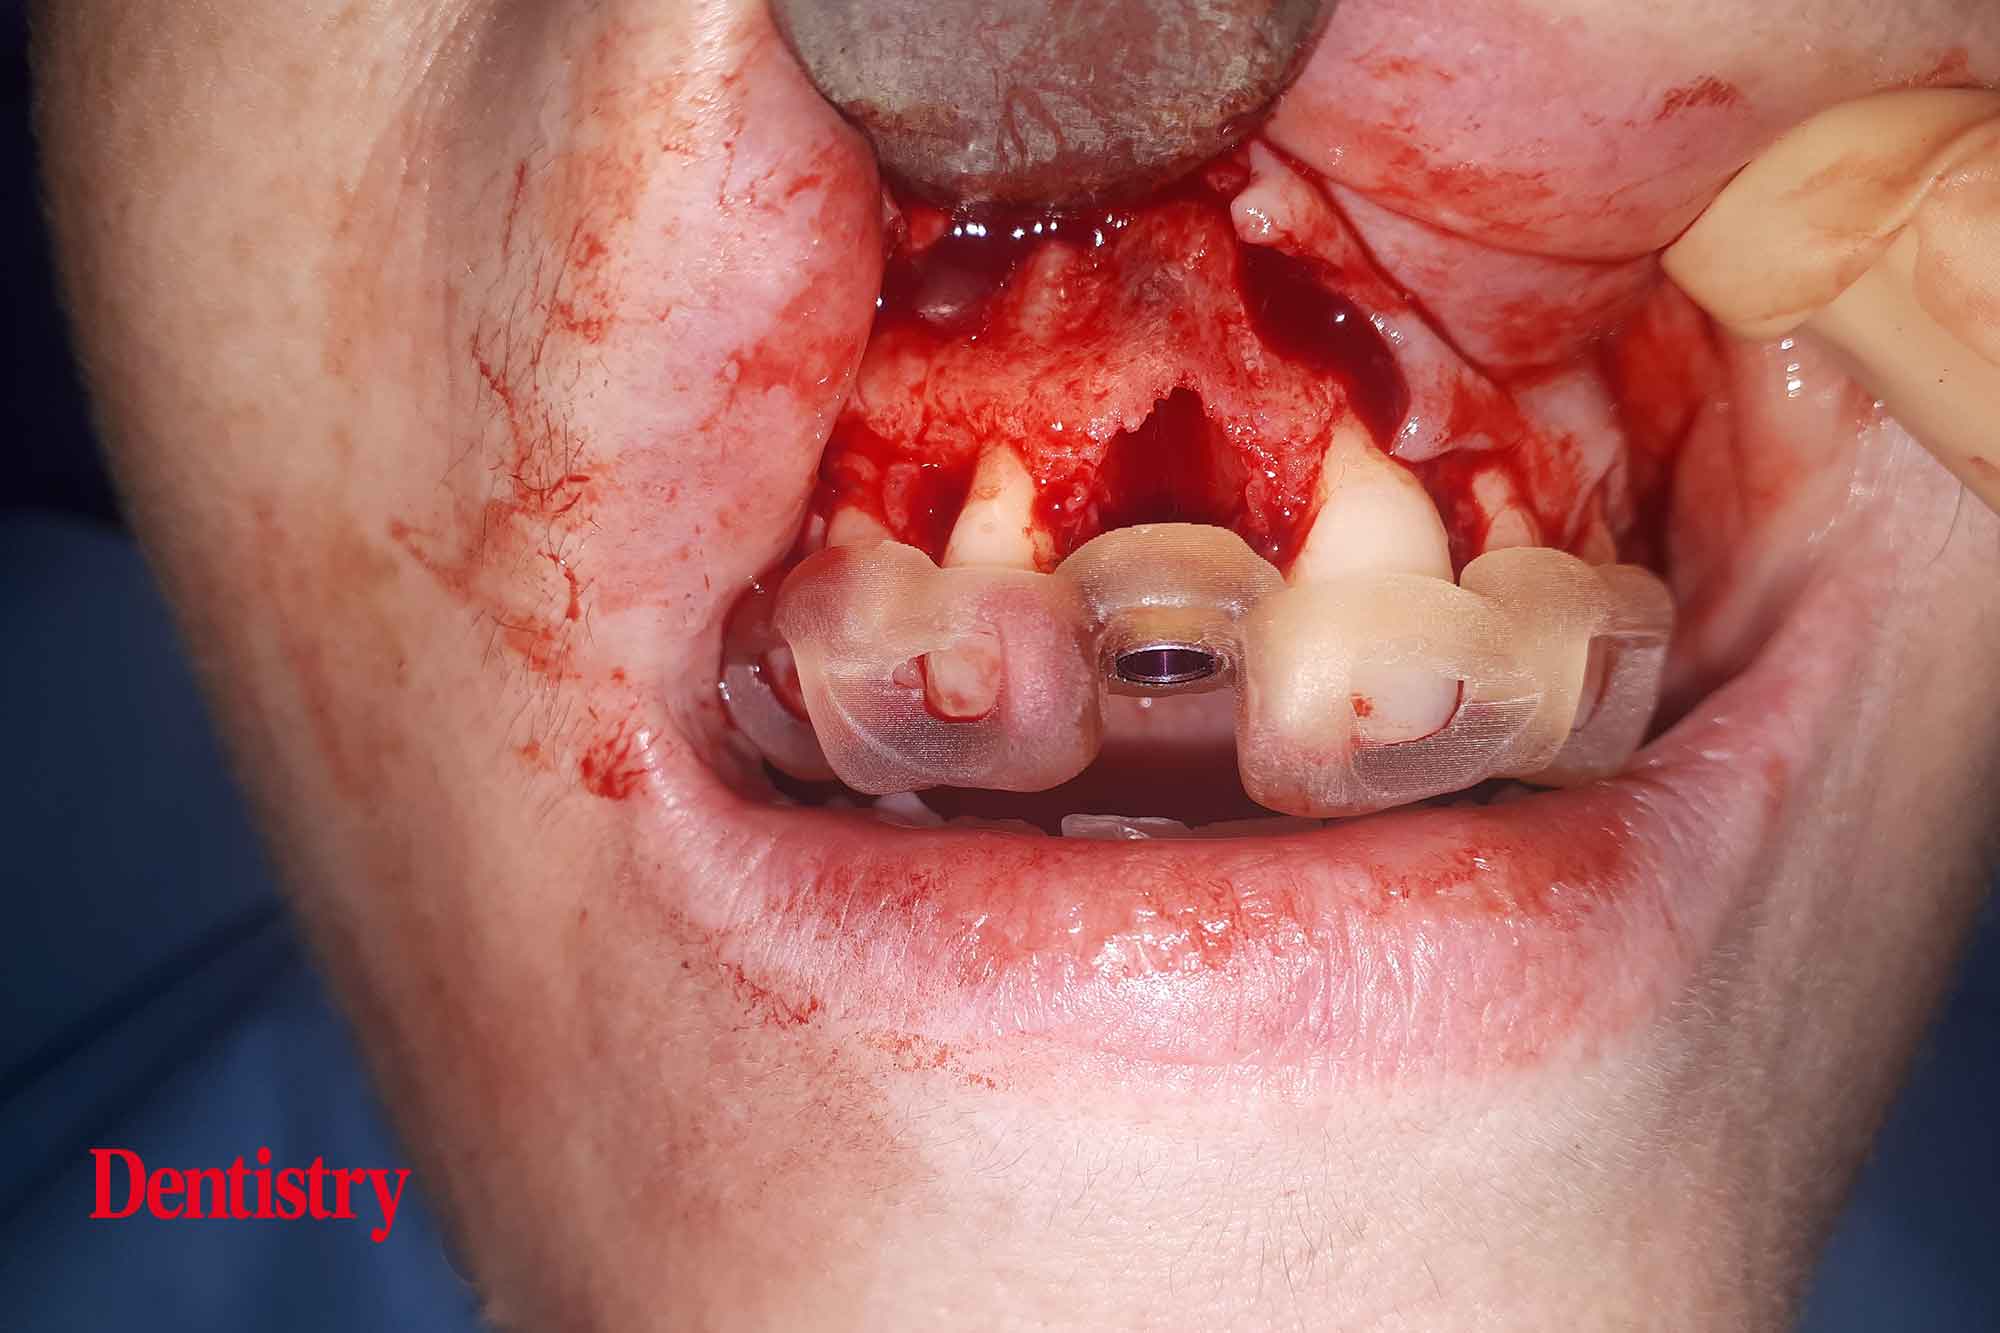

Local anaesthetic was delivered using articaine. Once the patient had confirmed the anaesthetic was working, a three-sided flap was raised. Buccal bone grafting was required and visualisation is key.

The root was then carefully removed, ensuring the buccal plate was left intact. The guide was then checked in place to confirm a passive fit.

Next, an osteotomy was prepared to the predetermined length, ensuring no lateral movements. The guide had been designed to engage both palatally and apically to the root socket.